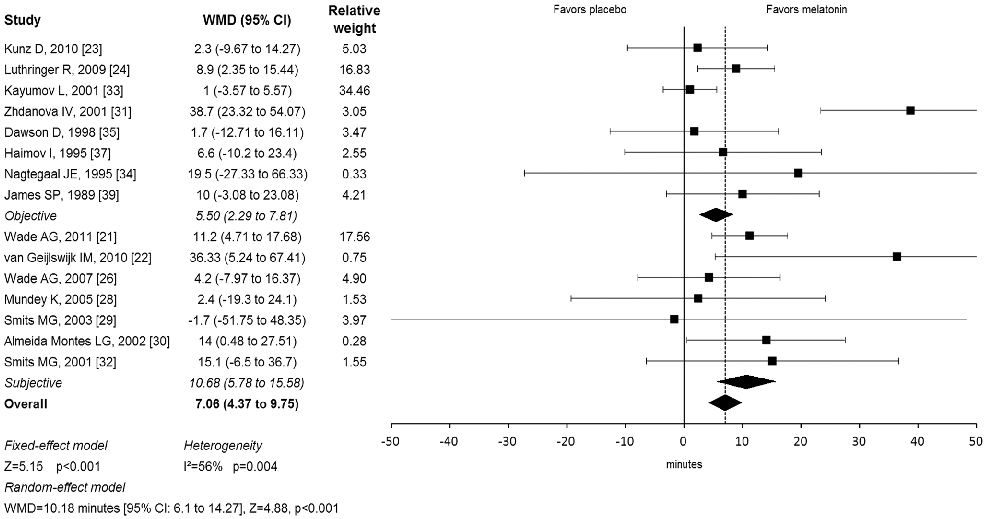

Forest plot from a meta-analysis of melatonin supplementation trials displays weighted mean differences in sleep onset latency, suggesting melatonin is associated with modest but statistically significant improvements in time to fall asleep.

Meta-analysis: melatonin for the treatment of primary sleep disorders.